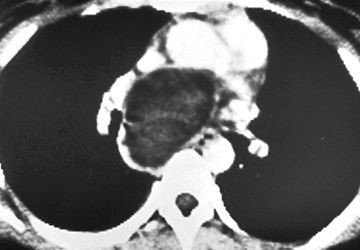

Sepsisli xəstələrdə rentgenoloji müayinədə mediastinumda hava görünməsi yüksək şübhə əlamətidir (Şəkil 9).

Şəkil 9. Mediastinal emfizema